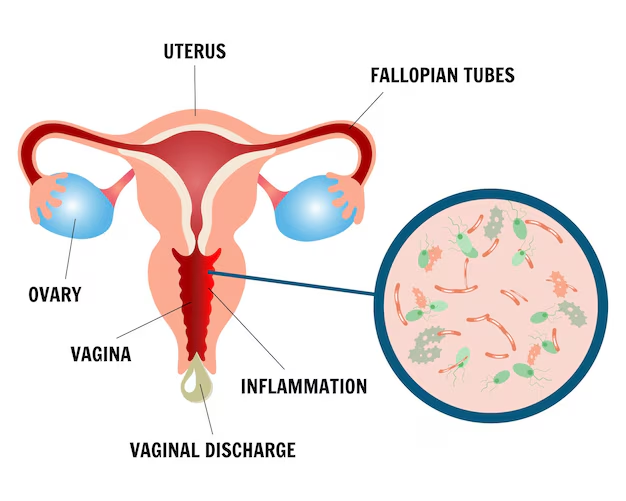

Women’s health requires a thoughtful and personalized approach at every stage of life. Our gynecology services are designed to diagnose, manage, and treat a wide range of gynecological conditions with accuracy, compassion, and advanced medical expertise. We provide comprehensive care for issues such as menstrual irregularities, pelvic pain, hormonal imbalances, reproductive health concerns, infections, fibroids, ovarian cysts, and other common and complex gynecological conditions.

Using modern diagnostic techniques and evidence-based treatments, our team focuses on identifying the root cause of symptoms rather than just managing them temporarily. Each patient receives an individualized treatment plan based on her medical history, symptoms, and overall health goals. From routine check-ups and preventive screenings to specialized treatments and minimally invasive procedures, we aim to deliver safe and effective care tailored to each individual.